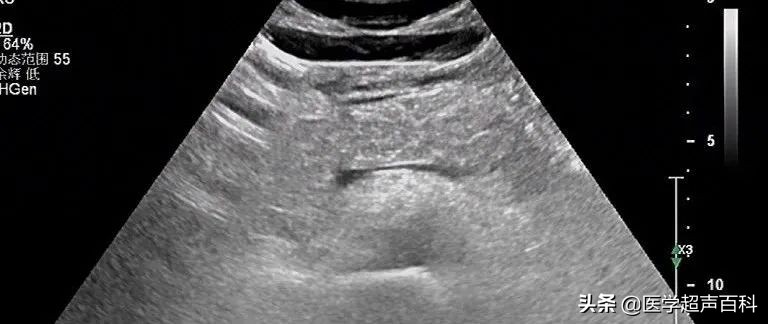

水肿型胰腺炎:胰腺弥漫性增大,边缘形态规整,内部回声减低,胰腺后方血管受压迫显示不清

急性胰腺炎声像图表现

(1)胰腺弥漫性或局限性增大,可失去正常形态,轮廓不清。

(2)内回声减低,呈弥漫分布的弱点状,中间有强弱不均、形态不整、边界不清的片状回声。严重水肿时呈透声暗区,似囊肿声像图。